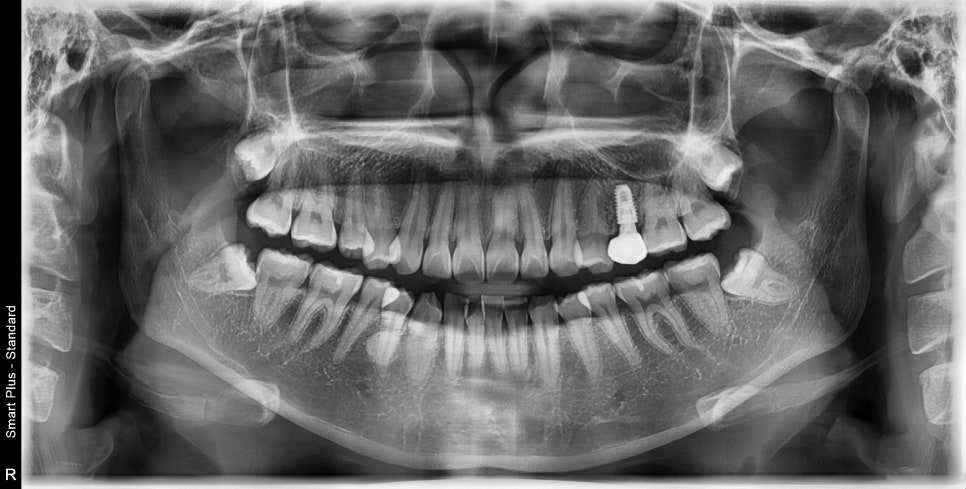

화살표 치아가 임플란트 였습니다.

한번의 재제작을 하셨고, 치료 후 임플란트는 머리부분만 새로 제작했습니다.

처음 교정을 하러 오셨을때는 기존의 임플란트 머리 모양을 '갈아서=삭제해서' 변형시킨 뒤 교정치료를 진행했고,

교정이 모두 마무리 된 이후에 머리만 바꾸었습니다.

나사를 모두 교체하거나, 제거하는 방법은 환자분이 너무 힘들어서 '나사'는 유지할 수 있으면 유지하고 있습니다.

그래서 이 분도 한쪽만 미니스크류를 식립했습니다